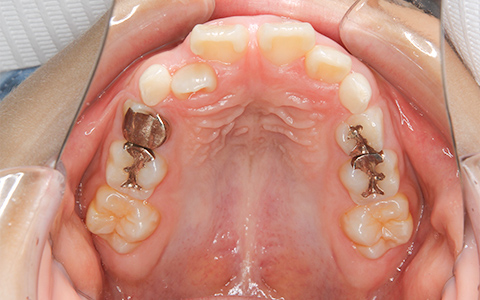

CASE.2

治療前

治療後

施術内容 ガタガタな歯並びのご相談でご来院(小児矯正時7歳 成人矯正時13歳)。叢生に対して、小児矯正(固定式拡大装置、セクショナルワイヤー)から成人矯正(マウスピース型矯正装置)に移行して対応した非抜歯治療

治療期間 小児矯正:1年7ヵ月、成人矯正:1年(通院23回)

費用 小児矯正:440,000円、成人矯正:480,000円

リスク・副作用 歯が動く痛み、歯髄壊死、歯根吸収、歯肉退縮、リテーナーを使用しないことによる後戻り